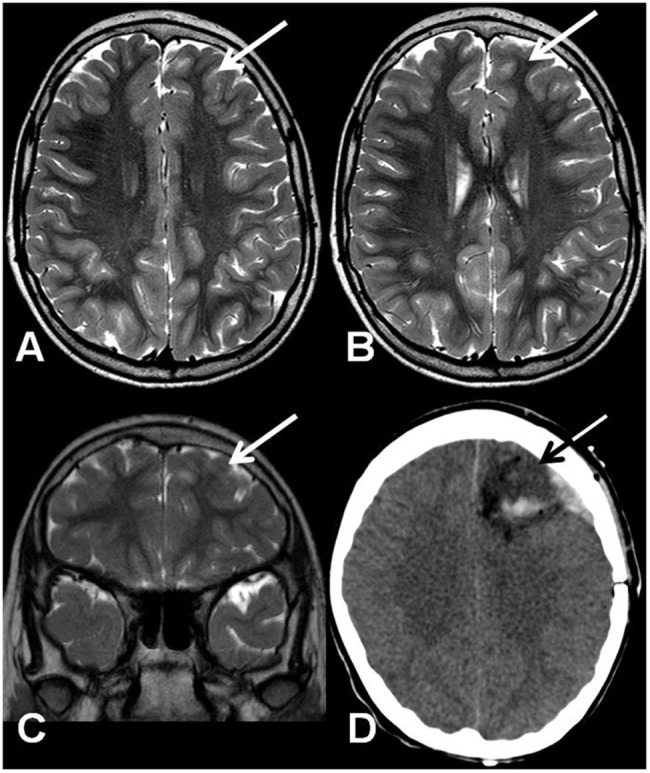

A 10-year-old girl was diagnosed with refractory epilepsy and left frontal dysplasia at 5 months of age. Prior to cannabinoid treatment she presented about three complex focal seizures. Treatment with phenytoin, topiramate, carbamazepine, levetiracetam, lamotrigine, primidone, and clobazam for appropriate periods and at adequate doses did not lead to seizure remission. The patient underwent focal resection of the left anterior frontal lobe at age 8 (Figure 1) and was seizure-free for 4 months. Her histological diagnosis after surgery was focal cortical dysplasia type 1b. After 4 months, seizures reappeared every day in the morning, despite treatment with topiramate, valproate, and clobazam. She was then started on an oral CBD-enriched extract (16% CBD, 208 mg/day or 6 mg/Kg/day; divided in three doses of 70 mg; in addition to topiramate 1 mg/kg/day, clobazan 0.4 mg/kg/day, and valproate 12.7 mg/kg/day), which eliminated seizures and improved general behavior, speech, understanding, and attention. After 4 months, the child started to present inappropriate laughter, ataxia, reduced attention, irritability, aggressiveness, spasms, and bilateral mydriasis with eye redness (Figure 2A). An analysis of the extract (which remained the same during the initial treatment) detected 4.03% of Δ9-THC and 89.6% of CBD, and a hair test showed the same concentrations of the two cannabinoids. The CBD-enriched extract was then replaced by the same dose of purified CBD (99.6%, dissolved in corn oil-BSPG-Pharm, Sandwich, UK) with no Δ9-THC, which led to complete improvement of all intoxication signs (Figure 2B) after 1 week, as assessed by clinical evaluation and EEG results (Figure 3), and to complete seizure remission after 4 weeks of the new treatment.